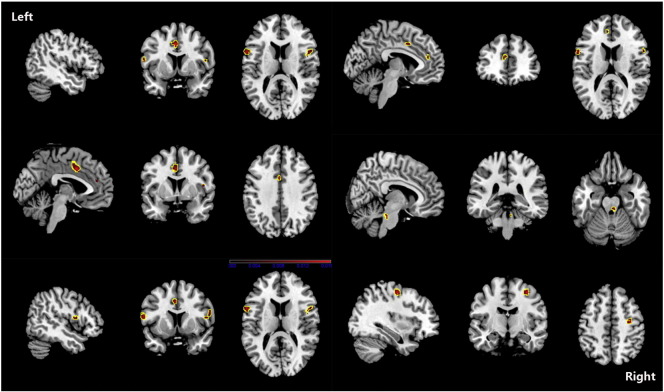

Although PAG increase was found in one study (Rocca et al., 2006), we found no overall increase in GM in patients with migraine. The ALE results showed that, compared with HC, migraine was associated with a common core set of decreases in GM volume in the bilateral inferior frontal gyri, the right precentral gyrus, the right cerebellar culmen, the left middle frontal gyrus and the left cingulate gyrus (see Fig. 2 and Table 5). Changes in the volume of GM in the right claustrum, left cingulated gyrus, right anterior cingulate, amygdala, and left parahippocampal gyrus were negatively related to the estimated frequency of attack (see Fig. 3 and Table 6).

Fig. 2.

ALE map investigating differences in GMV between migraine patients and HC. This image summarizes the results of all the papers involved in this meta-analysis. Red colour show grey matter decreases, they include bilateral inferior frontal gyri, right precentral gyrus, right cerebellar culmen, left middle frontal gyrus and left cingulate gyrus. (ALE maps were computed at a threshold of p < 0.001, with a minimum cluster size of K > 100 mm3 and visualized using MRIcron). Talairach coordinates of clusters showed in this image are reported in Table 5.

Table 5.

Regional difference of GMV between Migraine patients and HC.

| Cluster no. | Volume (mm3) | Weighted center (x, y, z) | x | y | z | ALE value (× 103) | Label | ||

|---|---|---|---|---|---|---|---|---|---|

| 1 | 672 | − 2.2 | 5.8 | 40.6 | − 2 | 6 | 40 | 16.268 | Left cingulate gyrus BA32 |

| − 2 | 0 | 46 | 9.502 | Left cingulate gyrus BA24 | |||||

| 2 | 488 | 33.4 | − 11.4 | 54.2 | 34 | − 12 | 54 | 16.521 | Right precentral gyrus BA6 |

| 3 | 392 | − 58.2 | 9.2 | 14.1 | − 58 | 10 | 14 | 31.043 | Left inferior frontal gyrus BA44 |

| 4 | 344 | 53.1 | 8.8 | 15.6 | 52 | 10 | 14 | 13.420 | Right inferior frontal gyrus BA44 |

| 56 | 12 | 16 | 9.479 | Right inferior frontal gyrus BA44 | |||||

| 48 | 4 | 12 | 8.818 | Right precentral gyrus BA44 | |||||

| 58 | 10 | 20 | 8.778 | Right inferior frontal gyrus BA45 | |||||

| 58 | 10 | 24 | 8.601 | Right inferior frontal gyrus BA9 | |||||

| 5 | 296 | 5.3 | − 30.4 | − 24.8 | 6 | − 30 | − 26 | 11.372 | Right cerebellum culmen |

| 6 | 120 | − 4.2 | 41.6 | 18.7 | − 4 | 42 | 18 | 9.696 | Left medial frontal gyrus BA9 |